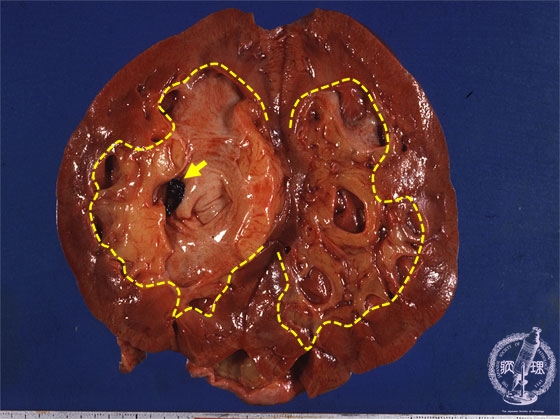

- (14)Nephrolithiasis

Gross findings: The renal pelvis contains a black-colored concretion (yellow arrow). This case also presents hydronephrosis. Note the dilated pelvis (yellow dotted line).